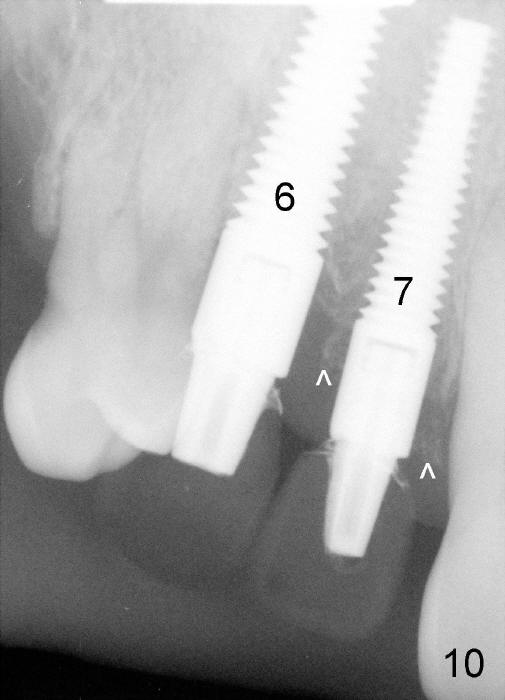

The patient is a heavy smoker. He reduces smoking prior to surgery. The most severely affected teeth (#6,7 and 9) are extracted and immediately replaced by 4x20 mm (#7, insertion torque 40/45) and 5x20 (#6,9, insertion torque over 60 Ncm) implants with (Fig.4,5). Straight (0 degree) abutments (3 and 4 mm, respectively) are rotated tightly into the wells of the implants by hand screw driver. In order to have reversibility to hybrid denture in the future, these abutments are not cemented. Heavy retention grooves are placed between the uniposts and implants. Provisionals are fabricated immediately and cemented temporarily. To increase stability, flowable composite is added to the area between the provisionals of #6 and 7.

The provisional of #9 is still wiggling a little bit buccolingually. It is probably due to loose connection between the implant and the abutment, although follow up PAs do not support it (Fig.7,8; ^: bone graft at the time of immediate implants).

Six months postop, the patient returns because of loss of the provisional at the site of #7 (Fig.9). In fact, all of the three abutments are loose. They are permanently cemented. The provisionals are temporarily cemented (Fig.10,11). Surprisingly, the bone graft appears to survive (^). One of it appears to fuse with the crest (Fig.11 *, as compared to Fig.8).